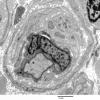

PERIPHERAL NEUROPATHY

18 HEREDITARY DISORDERS

Charcot-Marie-Tooth 1 (CMT-1) (3)